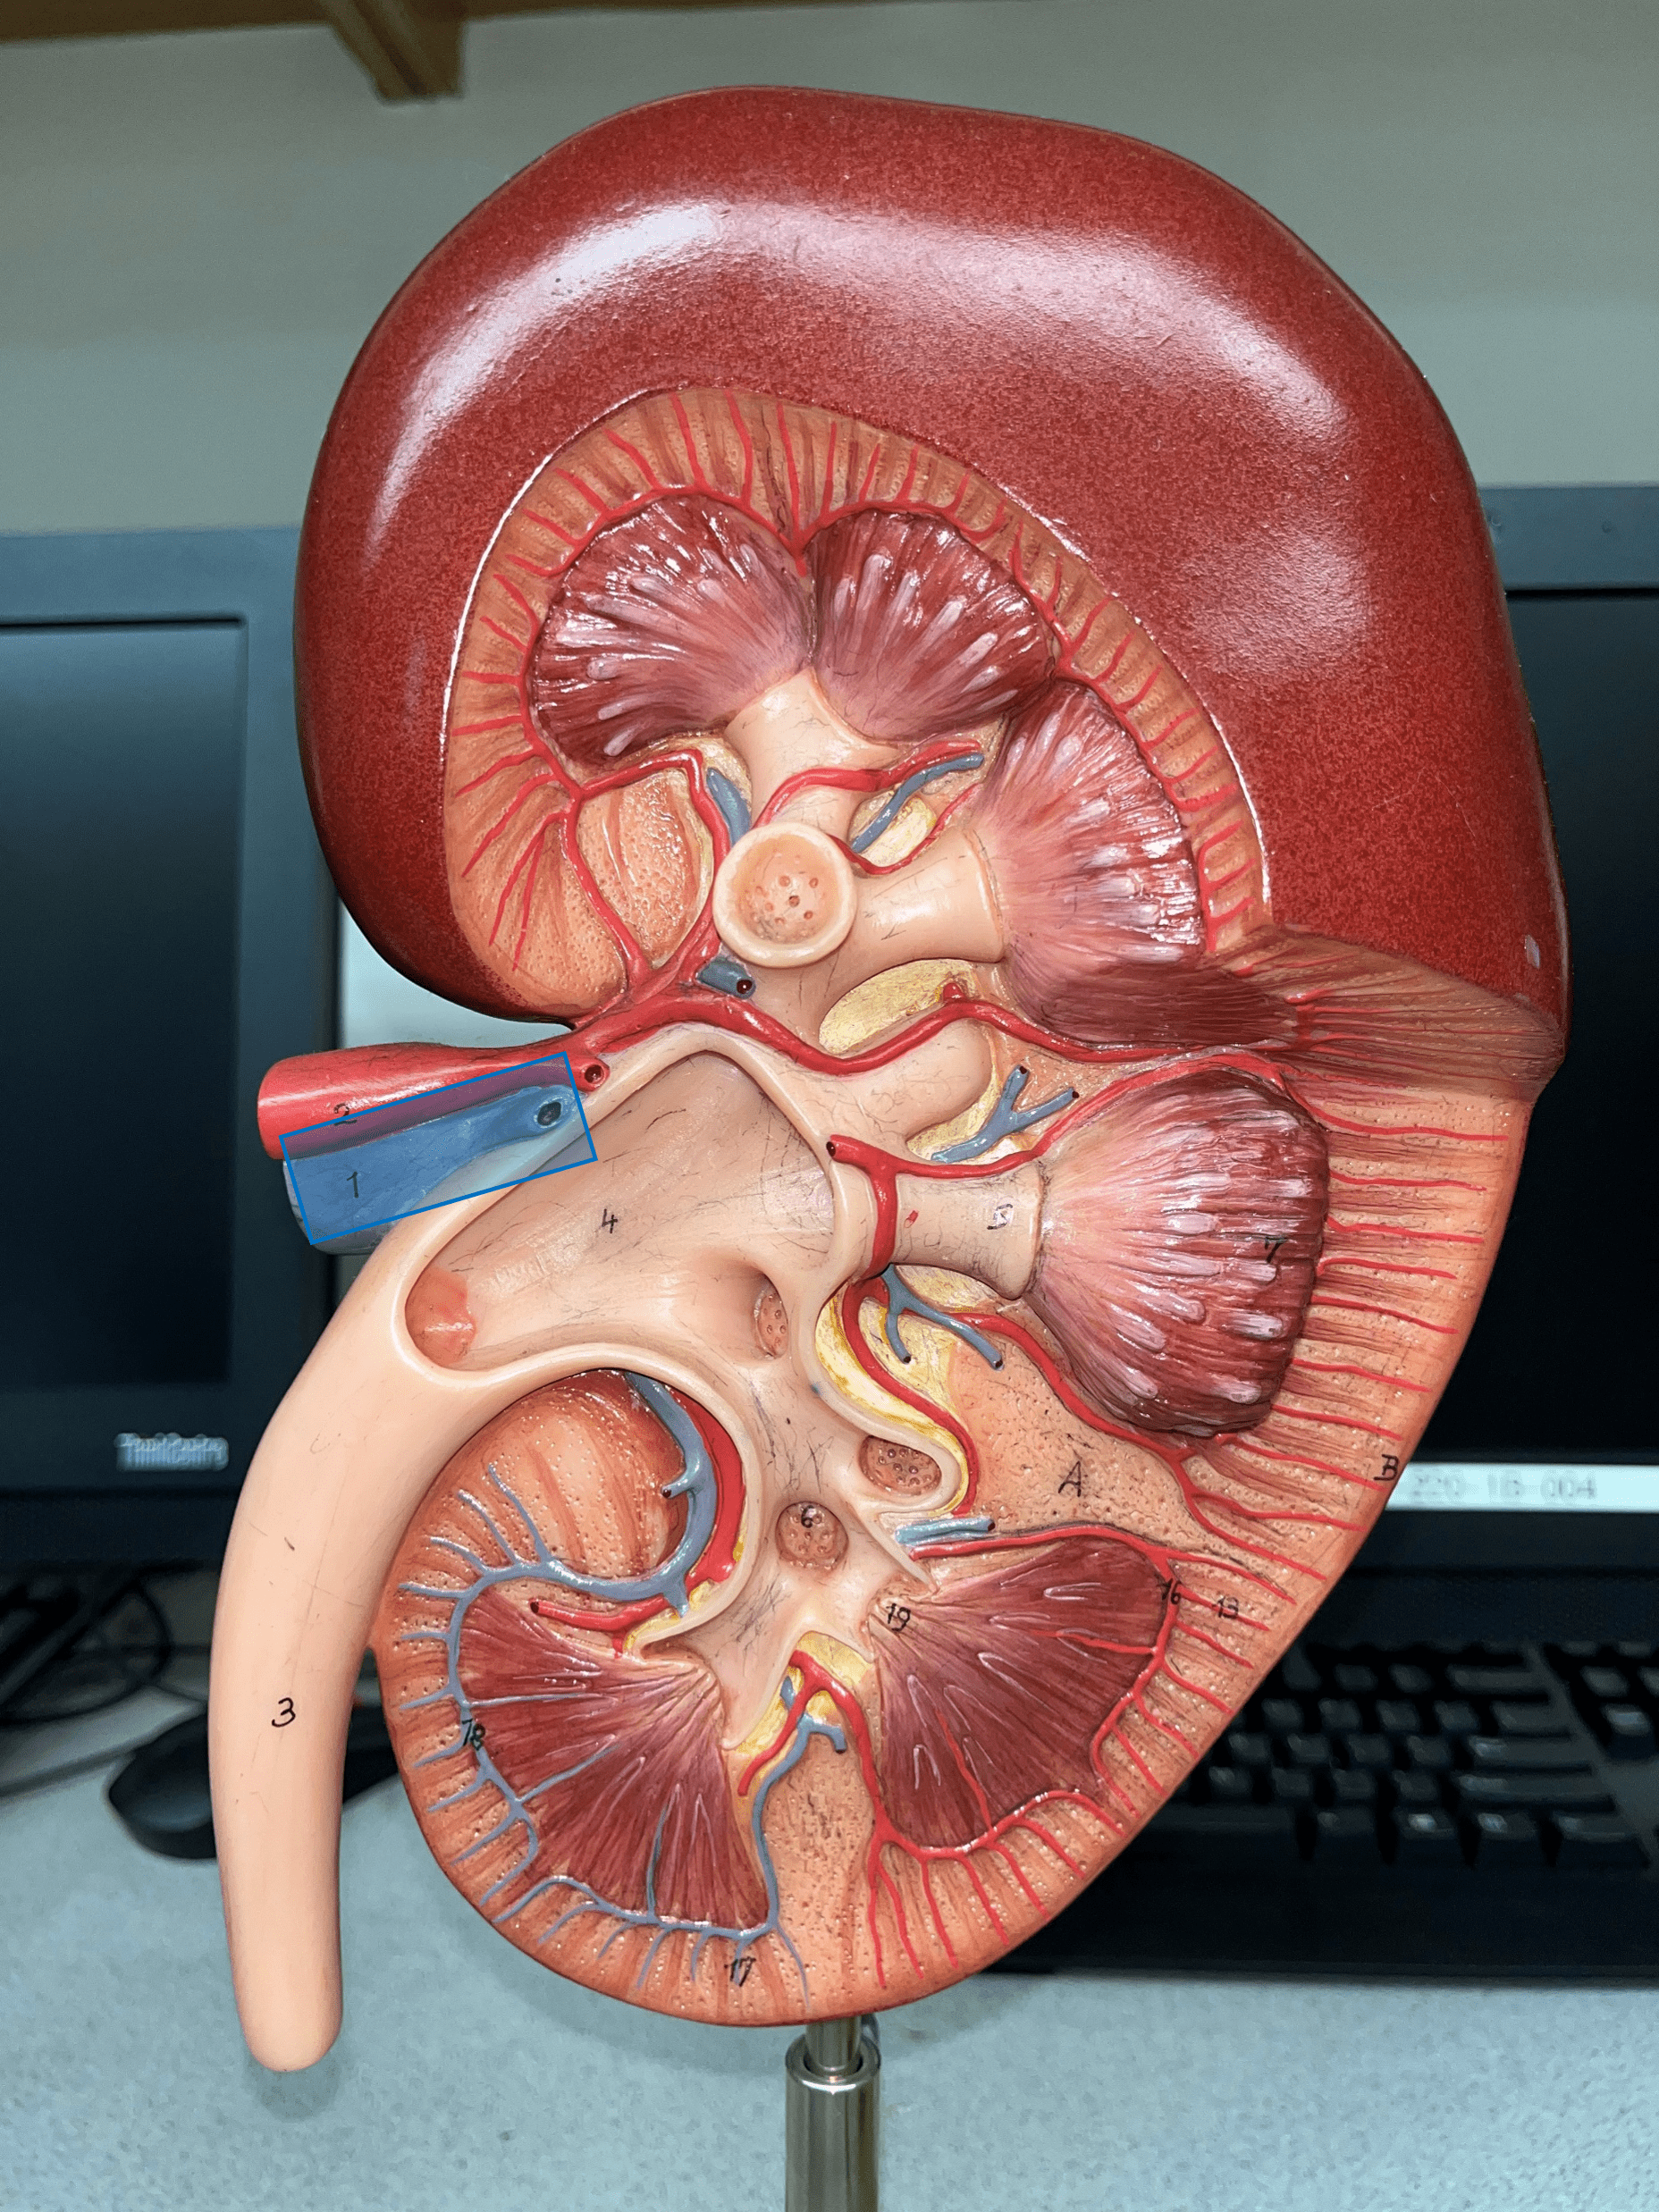

kidney

The organ that filters blood and excretes waste as urine.

renal capsule

The thin outer shell of the kidney.

renal hilum

• The concavity of the kidney.

• Admits the ureters, renal a., renal v., lymphatics, and nerves.

• Also known as the hilus of the kidney.

renal cortex

• The outermost region of the internal kidney.

• Superficial to the renal medulla.

• Appears slightly granular.

renal medulla

• The middlemost region of the internal kidney.

• Deep to the renal cortex and superficial to the renal pelvis.

• Contains triangular renal pyramids.

• Appears striated due to the presence of tubules and ducts.

renal pyramid

• A triangular structure found in the renal medulla.

• The base faces the renal cortex.

• The renal papilla (apex) faces the renal pelvis.

renal column

An area of granular tissue (similar to the cortex) between renal pyramids.

minor calyx

• A cup-like extension that collect urine from the renal papilla.

• Converges with others to form a larger major calyx.

major calyx

• The convergence of several minor calyces.

• Drains into the renal pelvis.

renal pelvis

• The innermost region of the internal kidney.

• Collects urine from the major calyces and drains it into the ureters.

• Includes the minor and major calyces.

renal artery

• The largest a. of the kidney.

• Supplies the entire kidney.

• Branches into smaller segmental aa.

segmental artery

• Branches of the renal a.

• Branches into smaller interlobar aa.

interlobar artery

• Extends between the renal pyramids.

• Branches of a segmental a.

• Branches into smaller arcuate aa.

arcuate artery

• Extends along the base of the renal pyramids.

• Branches of an interlobar a.

• Branches into smaller interlobular aa.

interlobular artery

• Extends through the renal cortex.

• Branches of an arcuate a.

• Branches into an afferent arteriole of a glomerulus.

interlobular vein

• Extends through the renal cortex.

• Converges into an arcuate v.

arcuate vein

• Extends along the base of the renal pyramids.

• The convergence of interlobular vv.

• Converges into an interlobar v.

interlobar vein

• Extends between the renal pyramids.

• The convergence of arcuate vv.

• Converges into the renal vein.

renal vein

• The largest vein of the kidney.

• Drains blood from the entire kidney.

• The convergence of interlobar vv.